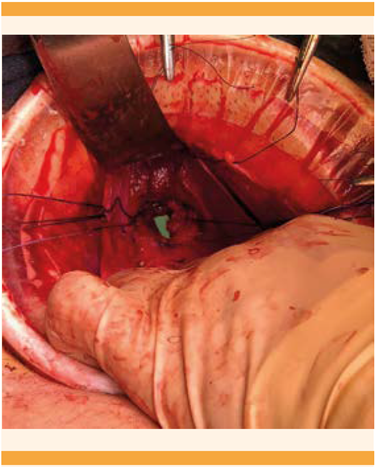

La laparotomía se practicó con incisión Pfannestiel y colocación de un separador tipo Alexis. Durante el procedimiento, el útero se encontró incrementado de tamaño, de 8 x 7 x 6 centímetros con finalización en fondo de saco ciego, múltiples adherencias laxas hacia el anexo izquierdo y colon sigmoides. Se procedió a liberar las adherencias útero-ováricas del fondo de saco e intestinales hasta lograr una adecuada movilidad uterina. Se procedió a la embrocación y colocación de un dilatador tipo Hegar en el canal vaginal como guía, que se palpó intrapélvico. Se identificó la distancia entre el fondo de saco ciego de la vagina y el útero de 1 centímetro. La comunicación entre el útero y la vagina se inició con la colocación de puntos de referencia en los extremos laterales de lo que se palpó como fondo de saco ciego de vagina (Figura 4). Se practicó una incisión y dejó a la vista el dilatador Hegar. Posteriormente se incidió en la parte baja del útero hasta exponer la cavidad endometrial; se obtuvo abundante líquido achocolatado proveniente de la ematómetra. Se terminó la evacuación y procedió a la aplicación de puntos simples en los bordes de la incisión uterina; en todos sus extremos se hizo un orleado para evitar tomar tejido endometrial. Se comenzó la unión del neo-cérvix con el canal vaginal y alrededor de toda la estructura y antes del cierre completo se aplicaron puntos simples con vicryl, se ferulizó la comunicación con una sonda Foley 22 (Figura 5) que permaneció durante cinco semanas posteriores a la cirugía. Se finalizó el cierre de la estructura (Figura 6), se verificó la adecuada hemostasia y se procedió al cierre de la pared abdominal.